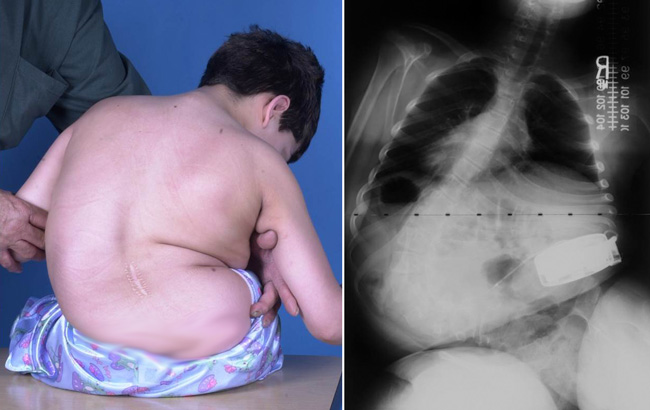

Η νευρομυϊκή σκολίωση επηρεάζει παιδιά με νευρομυϊκές διαταραχές και συνήθως χαρακτηρίζεται από κυρτώματα τα οποία επηρεάζουν πολύ μεγάλο τμήμα της σπονδυλικής στήλης (long curves). Εξαιτίας της μεγάλης ποικιλίας ασθενειών που μπορεί να προκαλέσουν μια νευρομυϊκή σκολίωση η κλινική εικόνα και η σοβαρότητα της κατάστασης είναι διαφορετική ανά περίπτωση. Παρόλαυτα, στις περισσότερες των περιπτώσεων υπάρχει διαταραχή της ισορροπίας και του συντονισμού του κορμού, του αυχένα και του κεφαλιού. Επιπλέον, κοινό σύμπτωμα των νευρομυϊκών σκολιώσεων είναι η κλίση της λεκάνης (pelvic obliquity), κατά την οποία η μία μεριά της λεκάνης σηκώνεται εμφανώς ψηλότερα από την άλλη. Συγκριτικά με την εφηβική ιδιοπαθή σκολίωση, οι νευρομυϊκές σκολιώσεις τείνουν να επιδεινωθούν γρηγορότερα, ενώ η πρόγνωση τους είναι χειρότερη σε όσο πιο μικρή ηλικία εμφανιστούν. Επίσης, όσο μεγαλύτερο το κύρτωμα κατά την διάγνωση τόσο μεγαλύτερη η πιθανότητα να επιδεινωθεί.

Οι χειρουργικές επεμβάσεις για τις νευρομυϊκές σκολιώσεις είναι περίπλοκες, εξαιτίας των βιολογικών αποτελεσμάτων λόγω της ασθένειας που δημιούργησε την σκολίωση, όπως η αναπνευστική δυσλειτουργία, η αδυναμία των οστών και η φτωχή θρέψη των ασθενών. Ανάλογα με το είδος της πάθησης, εφαρμόζεται πρόσθια ή οπίσθια σπονδυλοδεσία, που κάποιες φορές περιλαμβάνει μέχρι και την λεκάνη, όταν υπάρχει έντονη κλίση της από την μία μεριά. Η επέκταση της σπονδυλοδεσίας στο ιερό οστό γίνεται για να επιτευχθεί καλύτερη σταθεροποίηση, καθώς ο στόχος στις νευρομυϊκές σκολιώσεις δεν είναι τόσο η διόρθωση της γωνίας ή του αισθητικού αποτελέσματος, όσο η καρδιοαναπνευστική βελτίωση και η καλή λειτουργικότητα του ασθενούς.